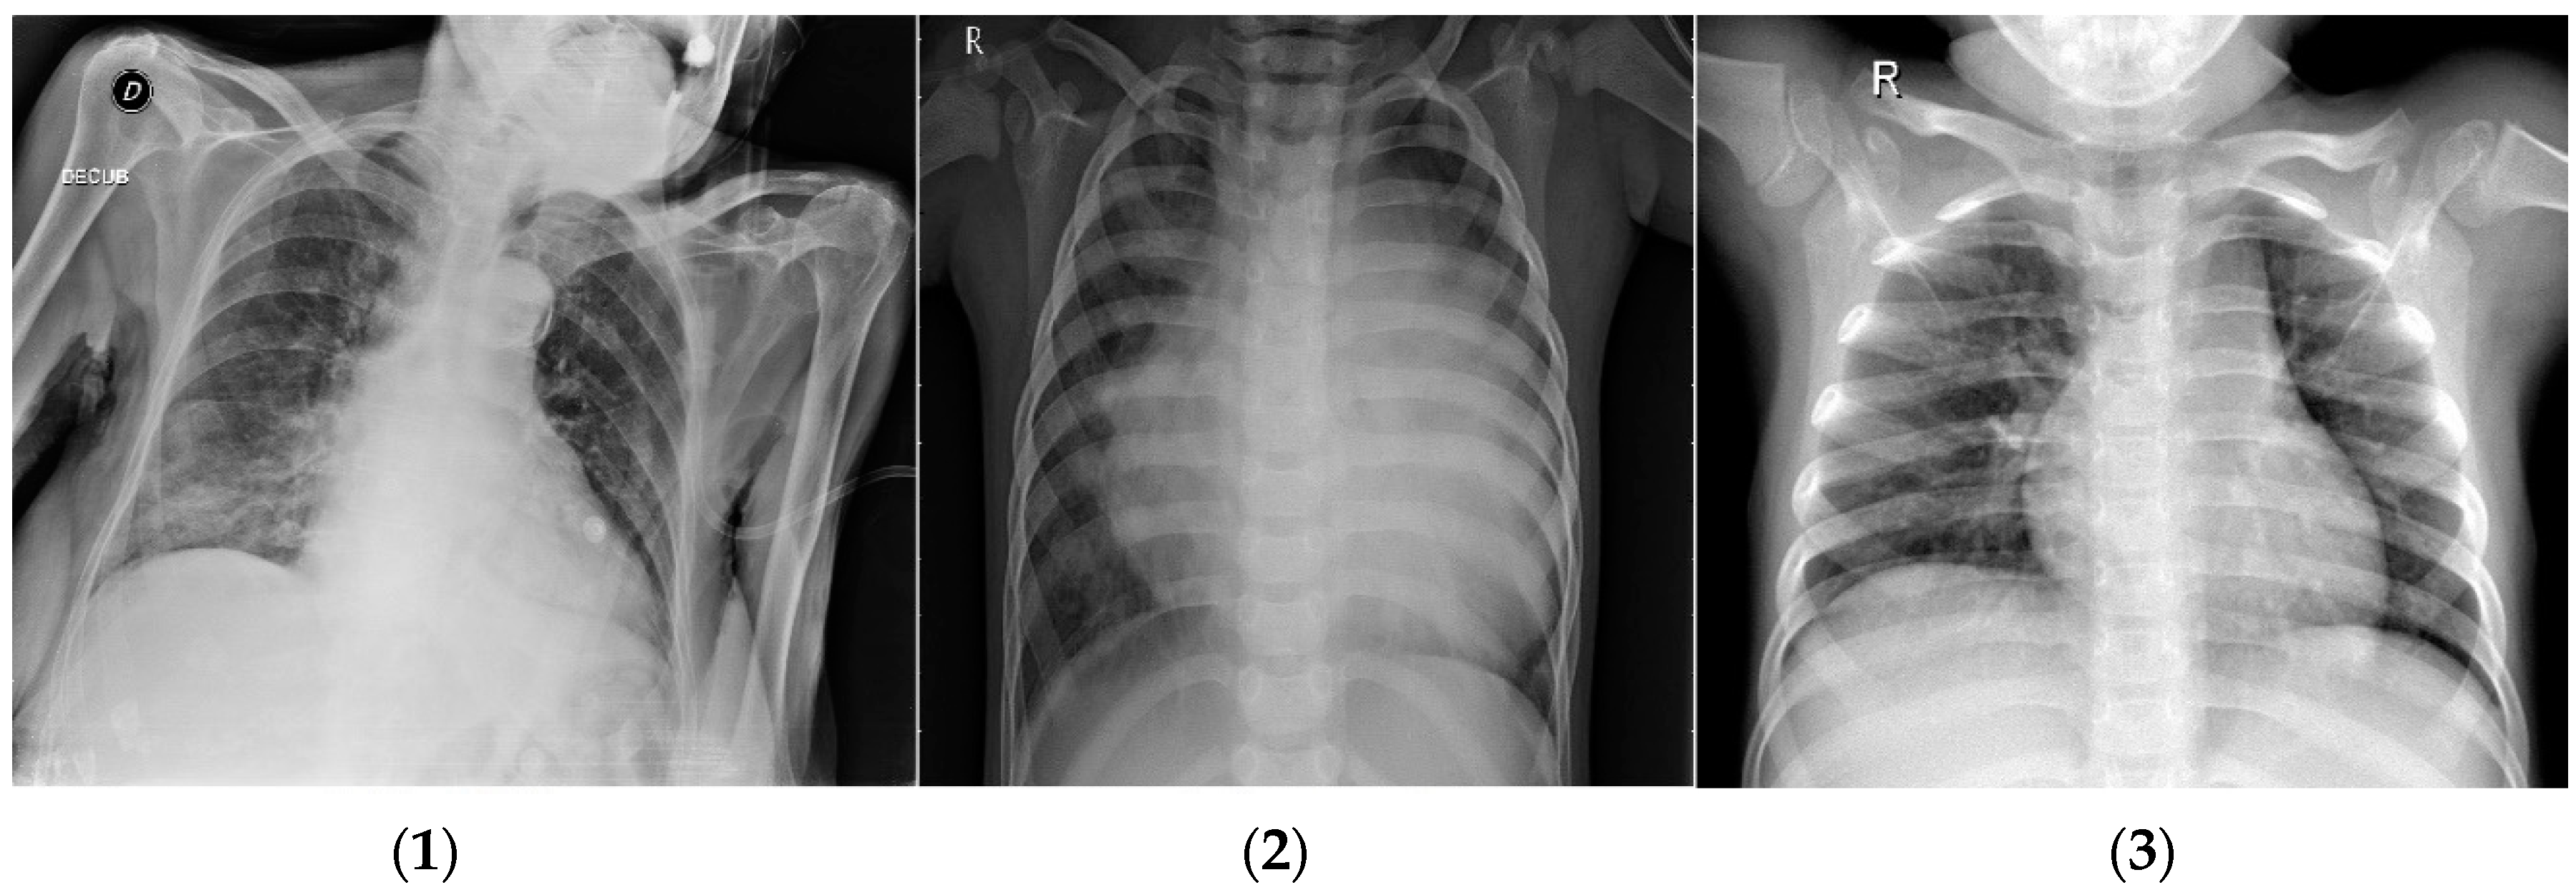

Figure 2.

Three classes of COVID-19 dataset: (1) COVID-19; (2) pneumonia, and (3) normal.

The dataset contains 6432 X-ray images in total [58]; image sizes vary and are not fixed. All images have been modified. This dataset is organized so that 80% is used for the training of total images and the remainder is used for the test dataset represented in Figure 1. It consists of three classes: COVID-19, pneumonia, and normal. These images are divided into 460 COVID-19, 3418 pneumonia, and 1266 normal images for the training and validation of the model. Also, we use 116 COVID-19, 855 pneumonia, and 317 normal samples to test the model. A sample from each class in the COVID-19 dataset is shown in Figure 2.